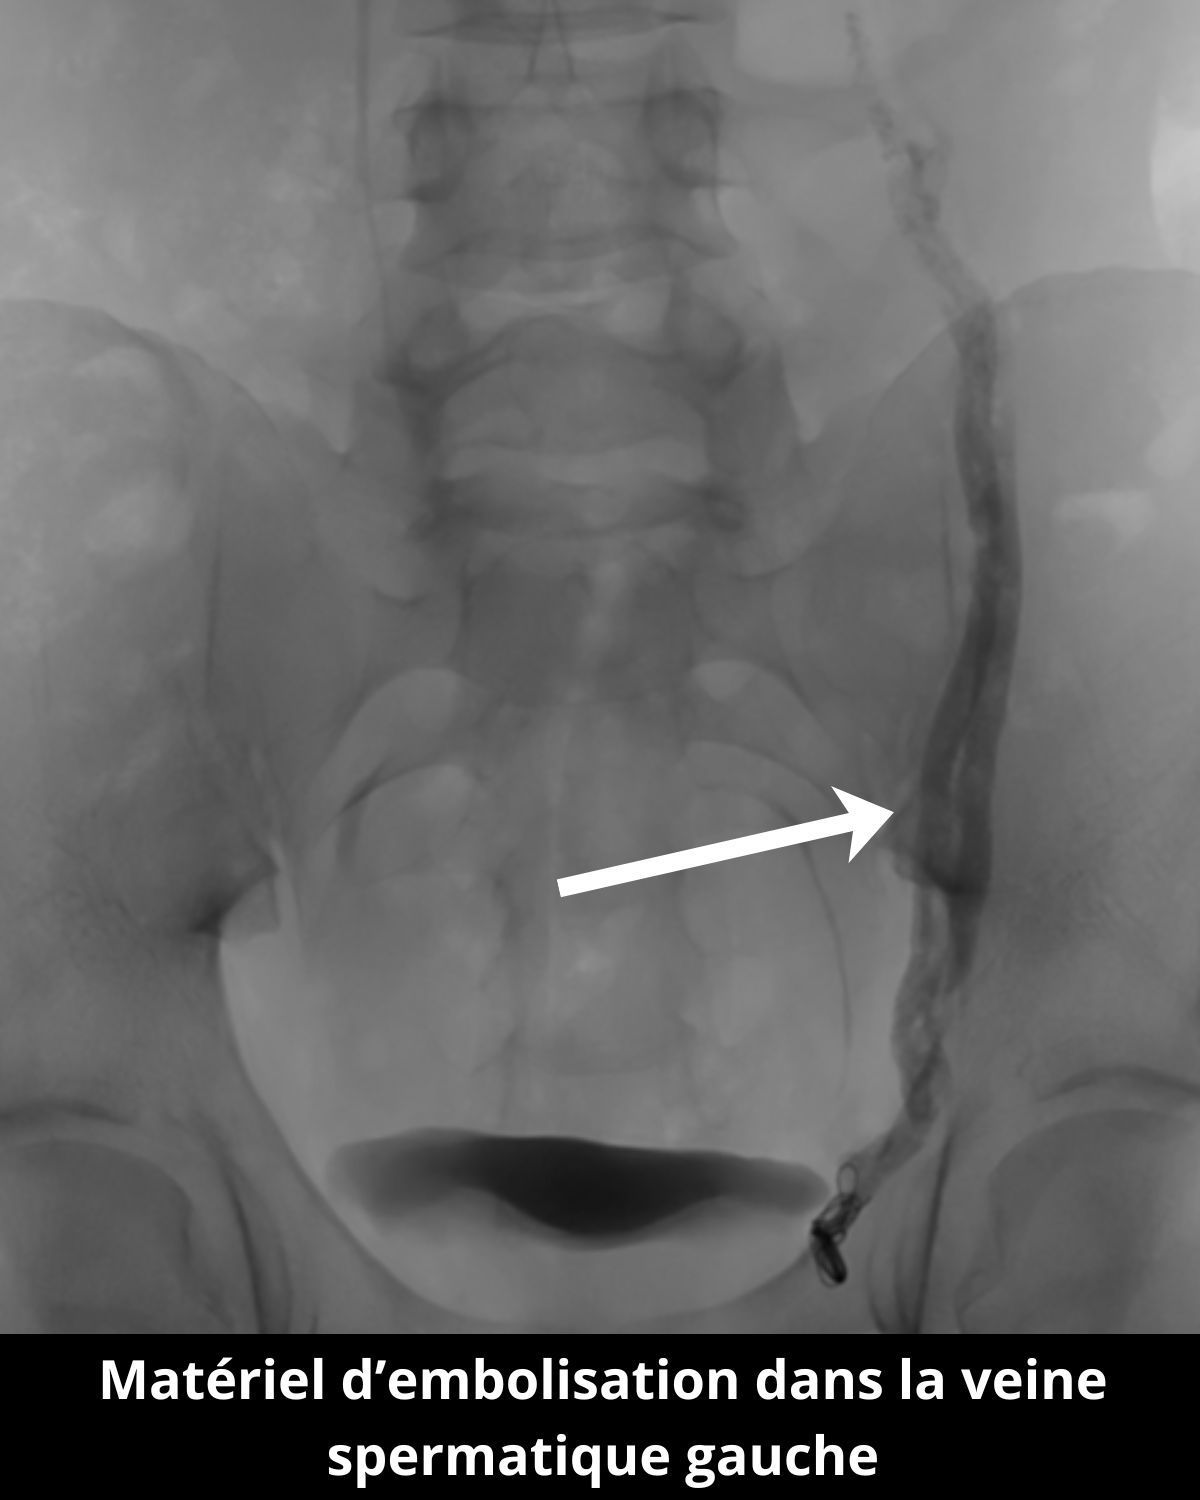

Ici le cas d’un patient consultant pour une infertilité depuis 2023.

Une petite ponction au niveau du pli de l’aine droit permet d’accéder à la veine spermatique pour la boucher de manière ciblée grâce à de la colle et des coïls, corrigeant ainsi le reflux responsable de la varicocèle.